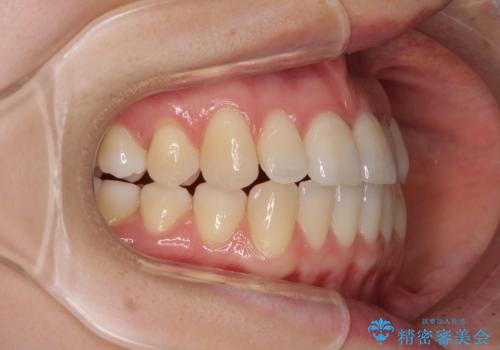

前歯のクロスバイト インビザラインによる矯正治療

- 前歯のクロスバイトを気にして来院された患者様です。

短期間での治療を希望され、ワイヤー装置とインビザラインとで悩んでいましたが、自己管理を徹底すると言うことでインビザラインによる矯正治療を行うこととしました。

しっかりとインビザラインの装着時間を守っていただいたので、1年弱で矯正治療を終えることができました。